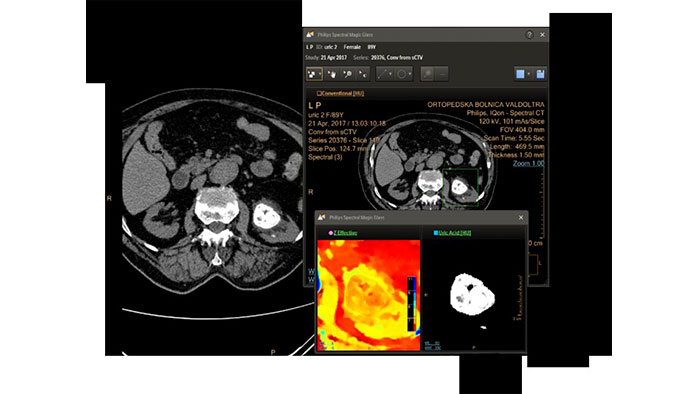

IQon Spectral CT is the only scanner to offer CT Spectral Light Magic Glass and CT Spectral Magic Glass on PACS, helping radiologists review and analyze multiple layers of spectral data at once, including on their PACS.

The spectral viewer is optimized for analysis of spectral data sets from the IQon Spectral CT Scanner. Obtain a comprehensive overview of each patient quickly and easily, quantify quickly, and assist in diagnosis. It is designed to accommodate general spectral viewing needs with additional tools to assist in CT images analysis.